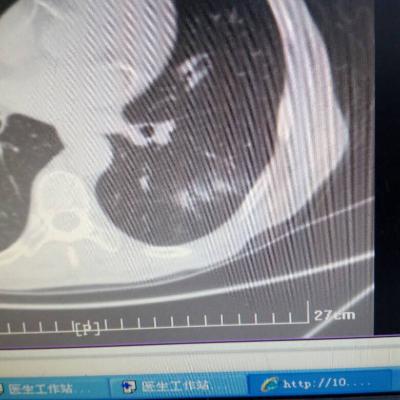

主诉:反酸、烧心5年,加重1年。 病史:患者5年前饮酒出现反酸烧心,并嗳气症状,剑突下烧灼感,饮酒及平卧后加重,无恶心呕吐,无腹痛腹泻,无吞咽困难,服用“达喜”后症状可缓解,易反复发作。3天前我科门诊示:胃镜反流性食管炎(LA-B),现为进一步诊治入院。

1.胃食管反流病 1.1反流性食管炎LA-B 2.食管裂孔疝 处理:患者诊断明确,行腹腔镜下食管裂孔疝修补术+胃底折叠术。

患者术后一周出院,反酸、烧心、嗳气症状明显缓解,无吞咽不畅等症状。 讨论:对于诊断有食管裂孔疝病人的胃食管反流病,且用药有一定疗效,建议行手术治疗,行腹腔镜下食管裂孔疝修补术,修补了膈裂孔,同时行胃底折叠术,加紧了贲门括约肌压力,共同形成抗“反流瓣”。